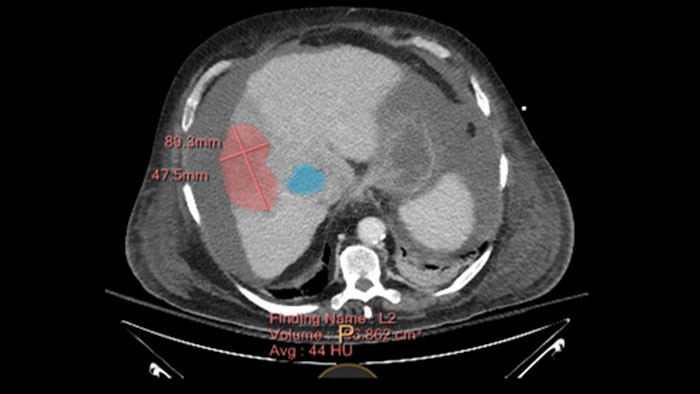

Semi-automatic tumor quantification

This semi-automated 3D (Volumetric) tumor response assessment tool, based on EASL (European Association for the Study of the Liver) criteria incorporates functional information from contrast-enhanced scans.

Inspection of tumors, as contrast enhanced, soft tissue oriented, and whole-body scans

Assists clinicians in viewing and evaluating CT images acquired on the IQon CT scanner for the inspection of tumors, as contrast enhanced, soft tissue oriented, and whole-body scans. It supports lesion viewing and analysis based on different spectral data types such as iodine density maps or virtual non-contrast-enhanced images.